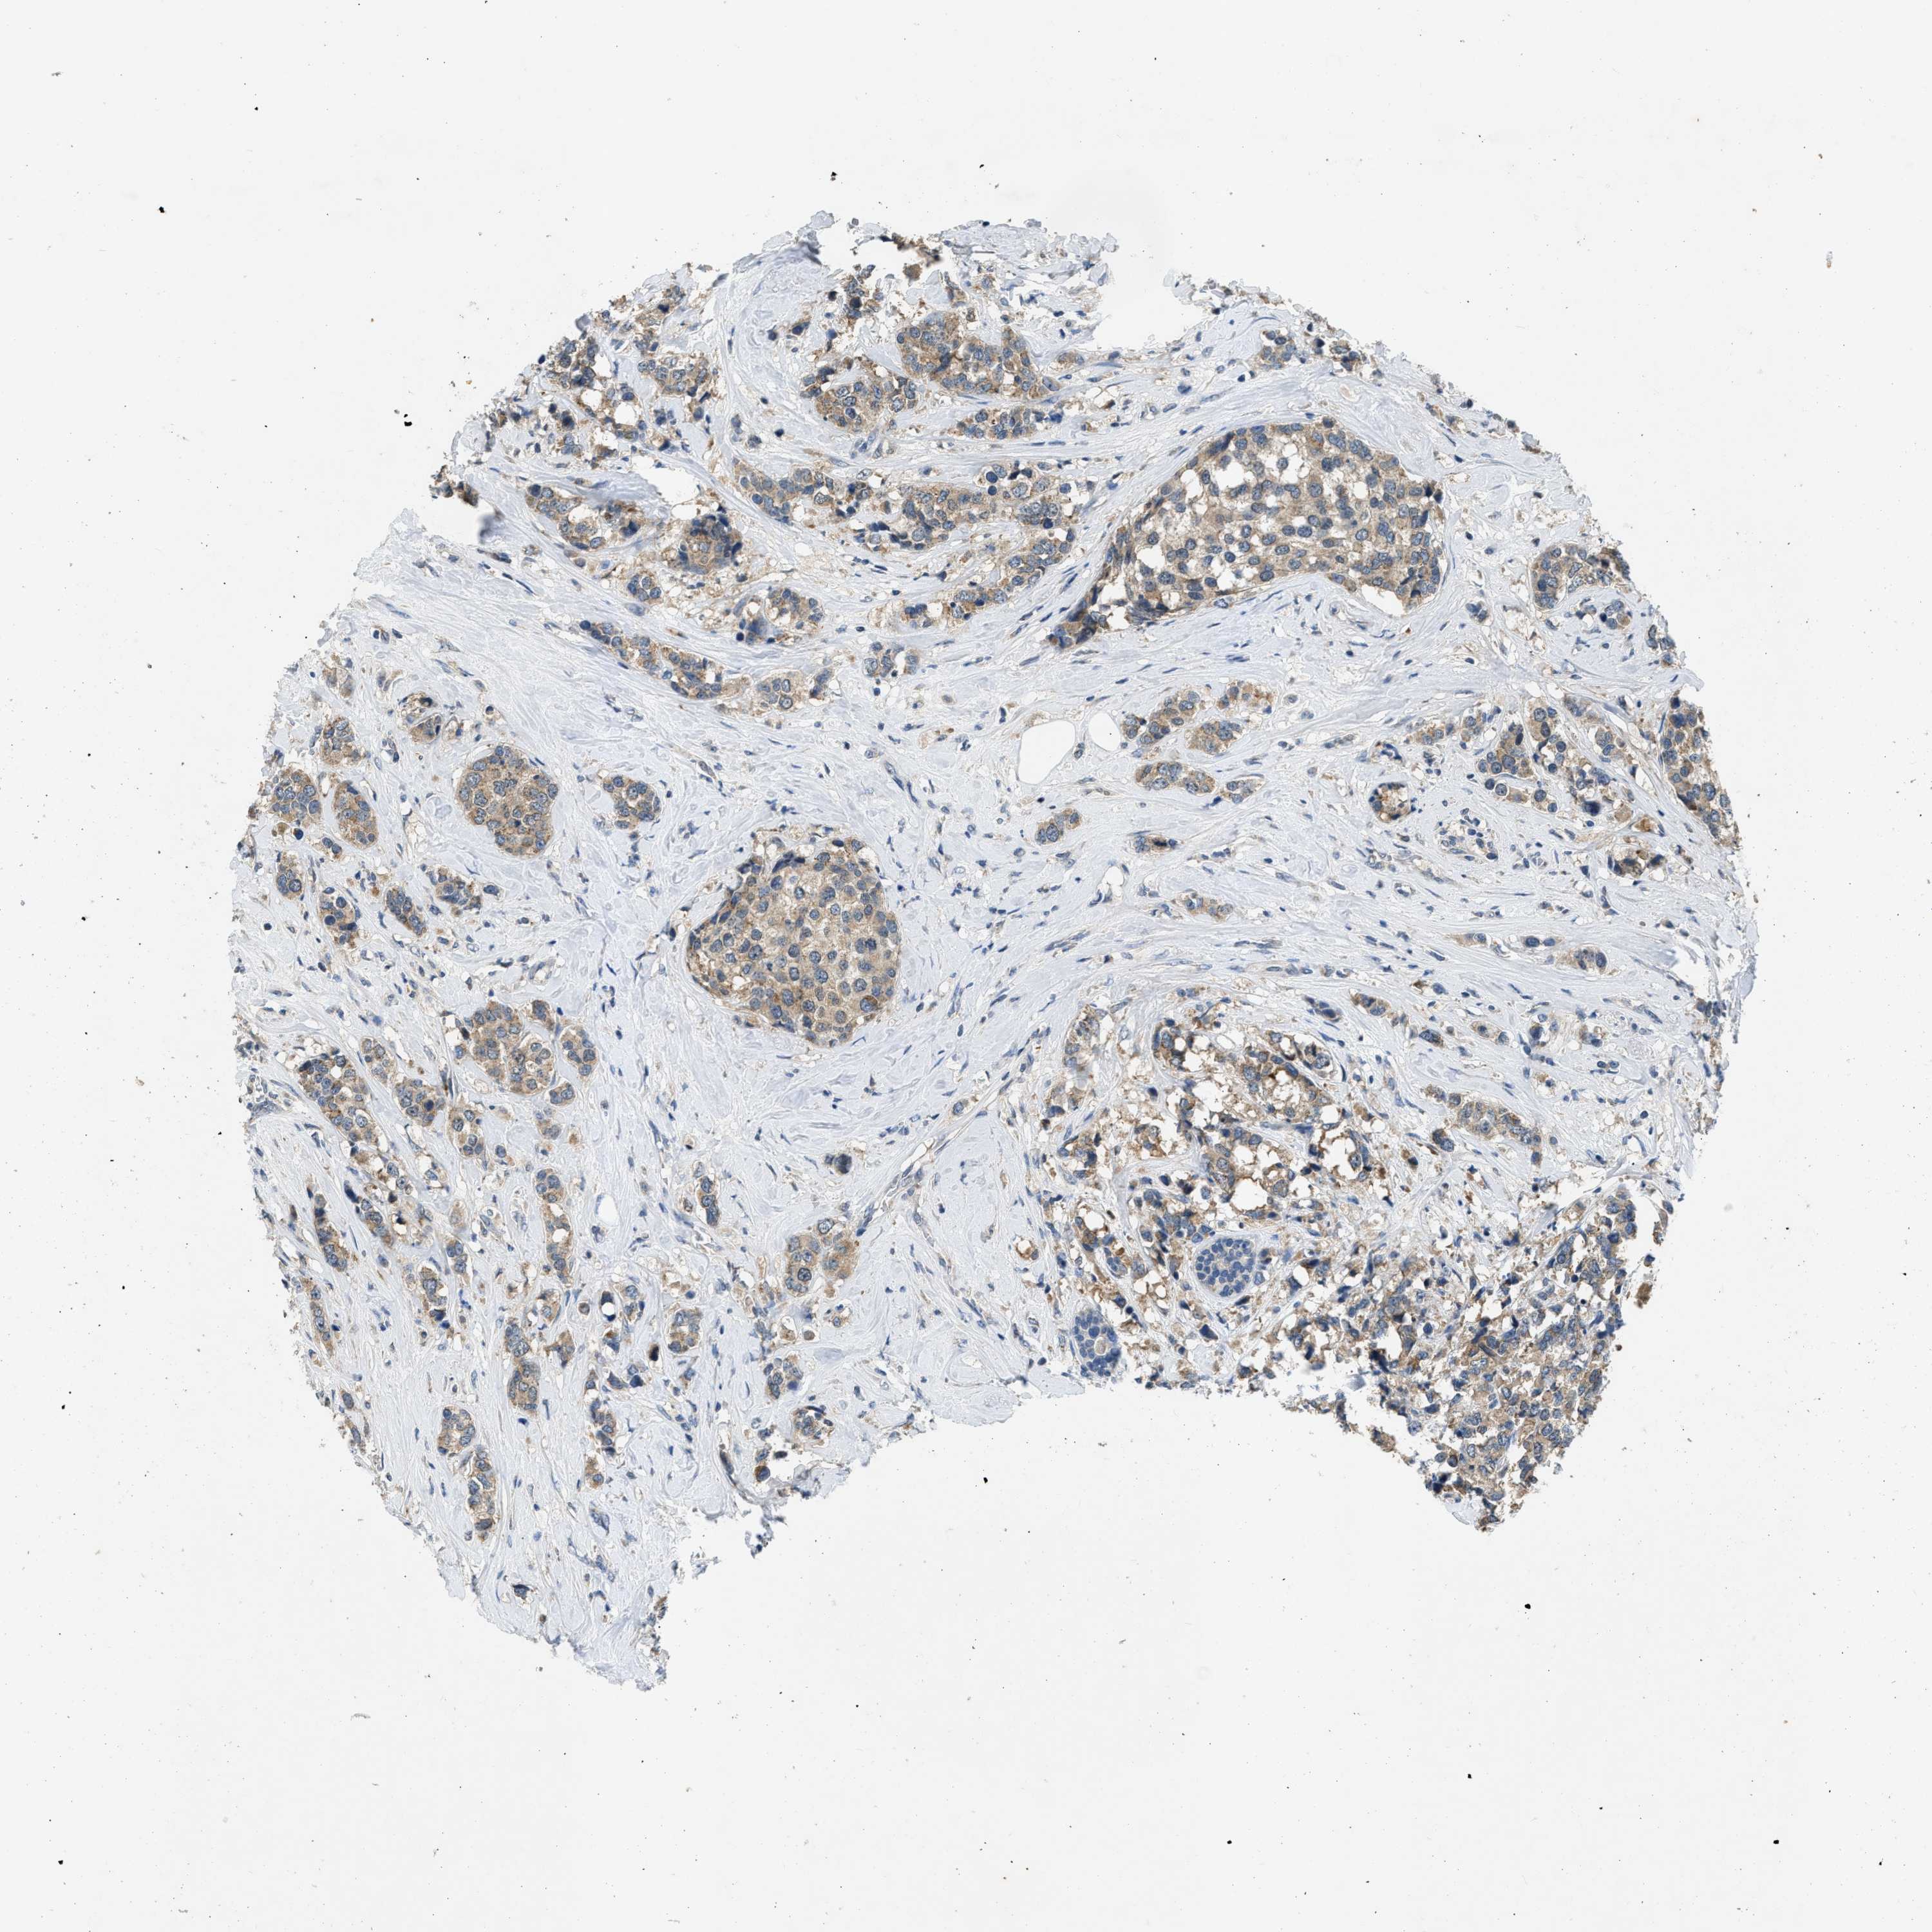

CANCER BREAST CANCER Show tissue menu

BRCA TCGA BRCA VALIDATION PROTEIN EXPRESSION